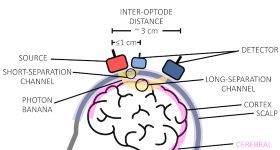

思影科技将于2024年8月19日--8月24日(周一—周六)在广州举办第四十二届近红外脑功能数据处理班(详见课表安排...

思影科技将于2025年7月30日—2025年8月4日(周三—下周一)在上海举办第五十一届近红外脑功能数据处理班(详见...